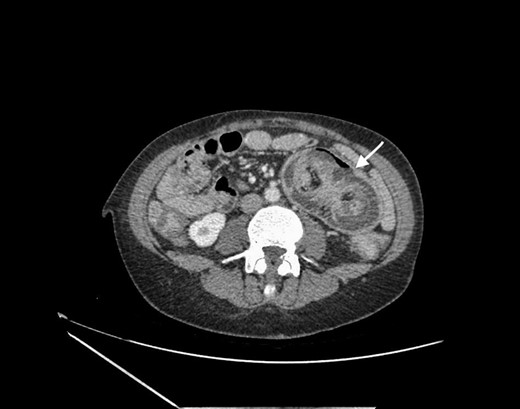

The clinical examination revealed normal vital signs and a moderate abdominal distention with tenderness at palpation in the left flank. Blood tests showed only a mild chronic anemia. The abdominal CT scan showed dilated small bowel loops located in the left abdomen and a ‘target’ sign suggestive of intussusception (Fig. 1).

Abdominal CT scan showing small bowel intussusception with the target sign (white arrow).